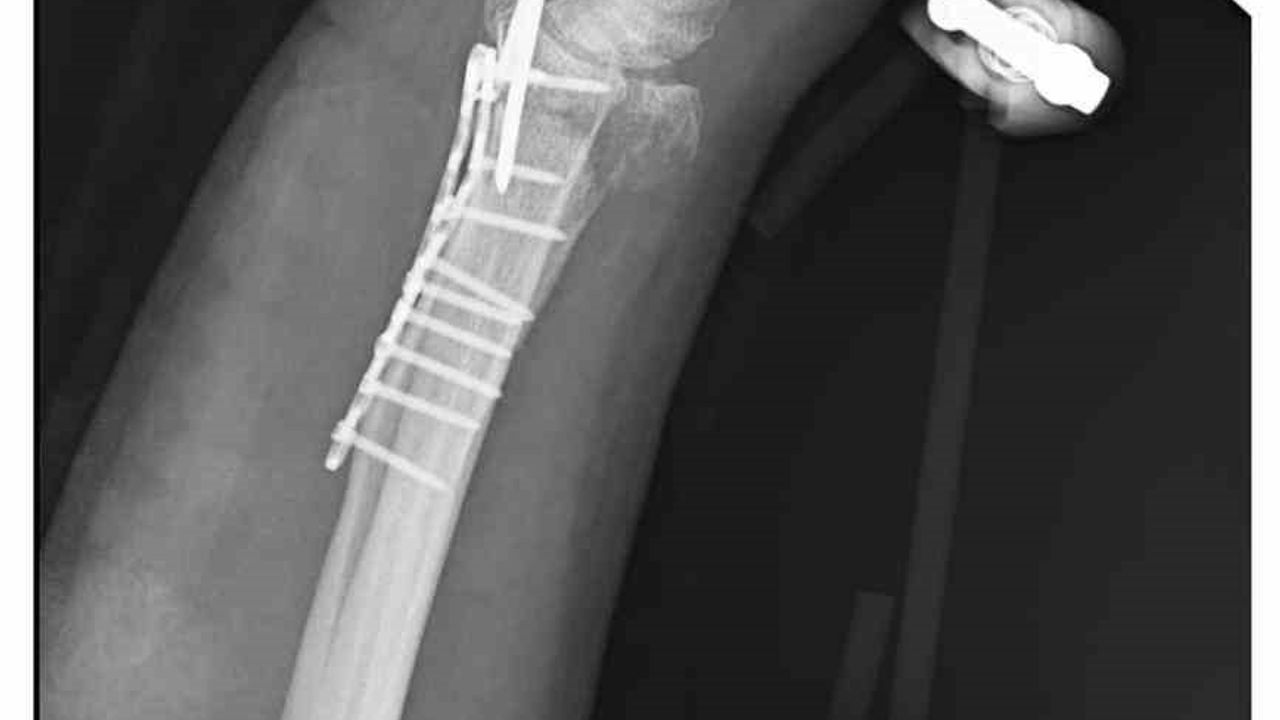

'Bileğimde 15 dikiş ve 11 platin var'

Yasin Arslantaş, 'Sabah apartmandan çıkış yaptığım sırada arkamdan 9 köpeğin geldiğini gördüm. Saldırgan haldelerdi. Bana saldırmak üzerelerdi. Kaçmaya çalışırken ayağım kaydı ve düştüm. Bileğimde 15 dikiş ve 11 platin var. İki ay boyunca kolum bu halde kalacak ve ardından da yine 2 buçuk ay fizik tedavi süreci olacak. Doktorlar his ve hareket kaybımın olacağını söylediler. Bileğimden büyük kemiğin kırılmasından dolayı zorlu bir süreç geçiriyorum. 3 saatlik bir ameliyat geçirdim' dedi.